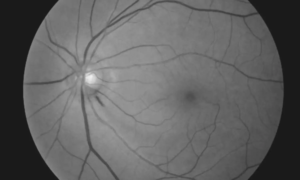

Nocturnal Blood Pressure Dips Linked to Rapid Central Vision Loss in Normal-Tension Glaucoma: Study

Korea: Patients with normal-tension glaucoma (NTG) who experience…